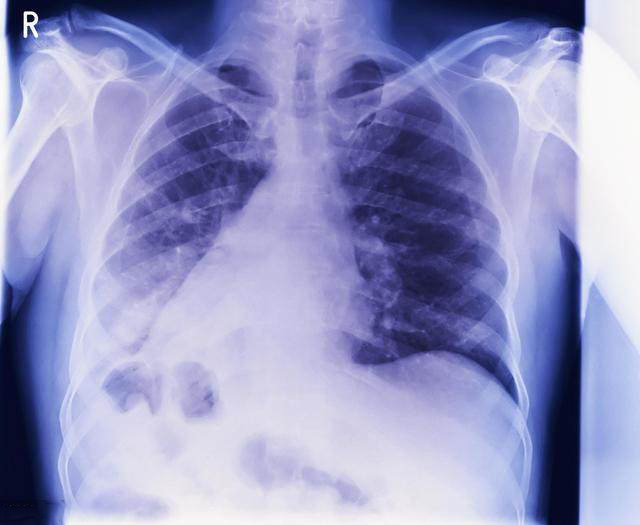

7、乳房X光片检查

随着女性年龄增长,以50岁后女性中,乳腺癌发病率逐年升高,50-59岁患病率为2%,60-69岁患病率为3%。因此,1-2年做一次乳房X光片检查特别有用,尤其是有乳腺癌家族史的女性,检查中发现不明包块或形态异常,应及时就诊。